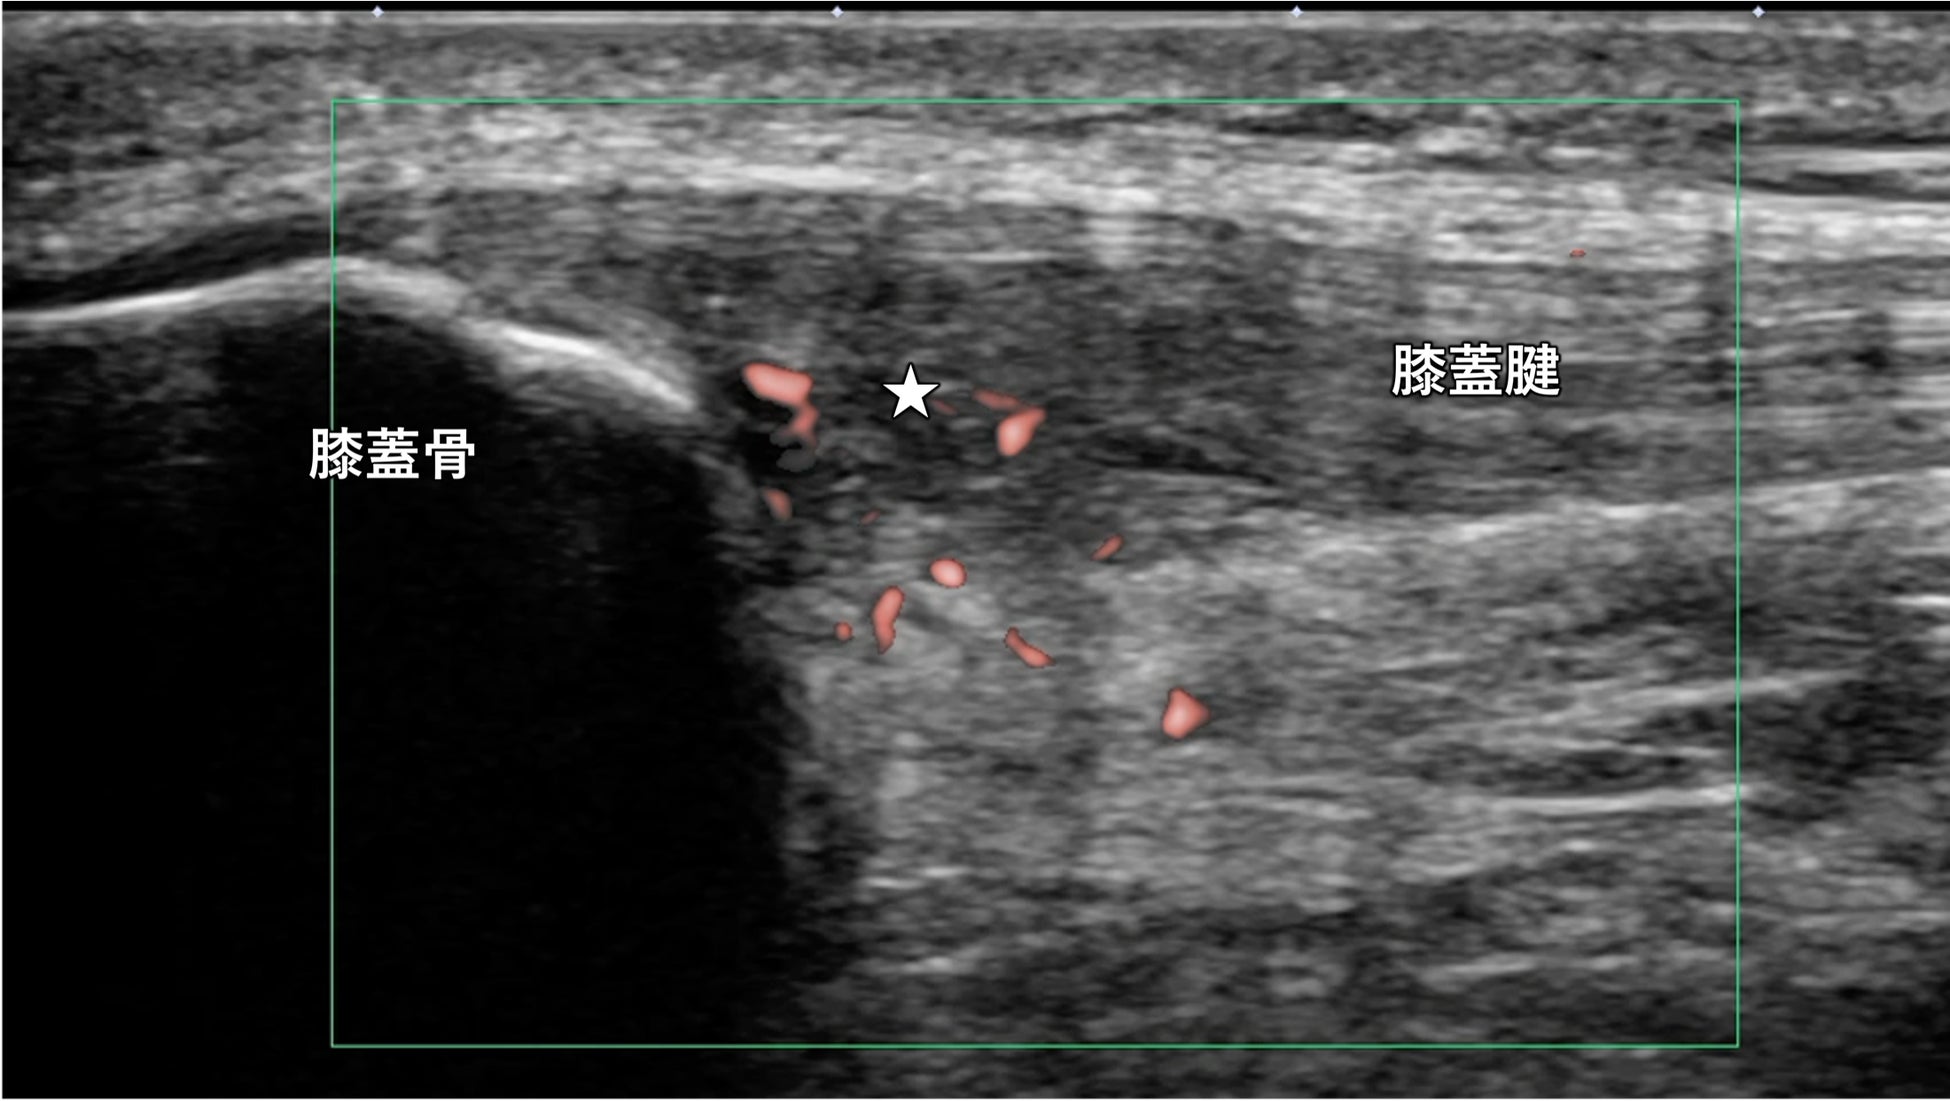

この難治性膝蓋腱症に対して、東京先進整形外科は「Percutaneous ultrasonic tenotomy(以下、超音波腱切離・剥離術)」を実施しています。この治療法は、使用する専用の機器のメーカー名からTENEX(テネックス)と呼ばれることもあります。

超音波腱切離・剥離術は、30分程度で終わる日帰り治療です。メスや内視鏡を使用せず、1.6mmほどの専用のデバイスを膝蓋腱の中に挿入して、腱内部の痛みの原因となっている変性組織を吸引します。傷は糸で縫う必要はなく、テープで保護して終わりです。治療後は、1週間の膝の固定・松葉杖による歩行により膝蓋腱への負担を減らします。リハビリテーションを行いながら徐々に運動強度を上げ、処置後3か月以降でスポーツへの完全復帰が許可されます。